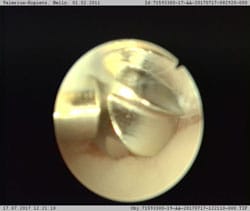

Computertomographie gilt als Goldstandard für eine sichere Diagnose von FPC (Abb. 3 bis 5). Arthroskopie (Gelenkspiegelung) erlaubt meistens ebenfalls eine gute Diagnose, ist aber eine invasivere Technik (Abb. 6).

In der Regel wird die Behandlung arthroskopisch (minimalinvasiv) durchgeführt. Dabei werden die gelösten Knochenfragmente und der erkrankte Knorpel entfernt (Abb. 7). Die Vorteile dieser Methode liegen darin, dass der Operateur eine deutlich bessere Übersicht erhält und dass sie wenig belastend für das Tier ist. In seltenen Fällen, z.B. bei sehr großen Knochenfragmenten kann es nötig sei das Gelenk durch einen kleinen Schnitt zu eröffnen.